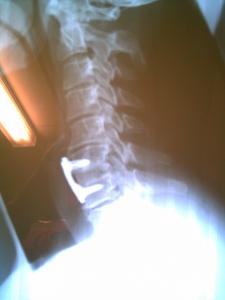

Mine was a break at C5 C6 with severe shoulder stresses. The shoulder aches in cold damp weather. Heels for me since recovery helps keep the "lazy" posture away and tightens everything reducing a large amount of aches that start in the shoulder and then hit the neck muscles like a hammer. The neck work - bone graft and plate are fine but does restrict my throat. As advised recover first - listen to your surgeon and take advise as it goes. It may not be the wearing but a slip or trip could cause far more than you need. Take Care Al